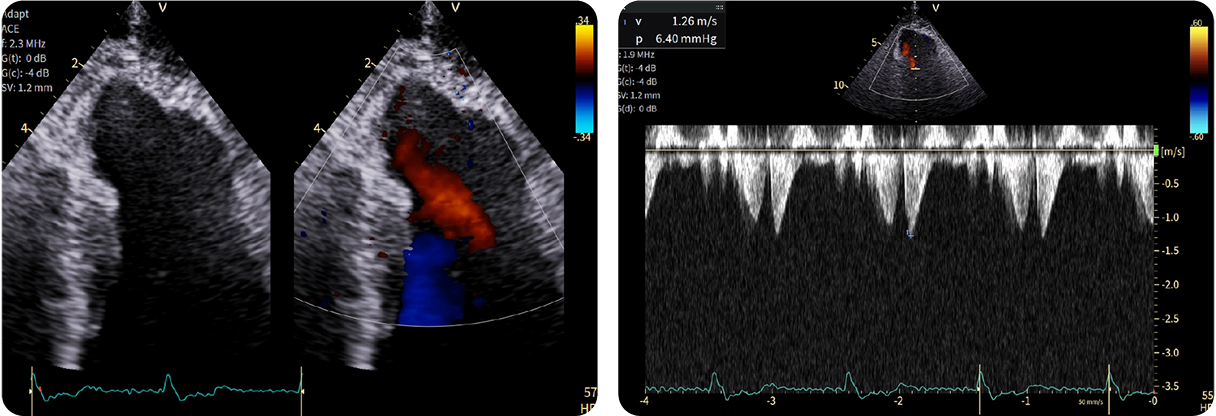

1-Beat Cardiac migliora la qualità diagnostica dell’angio-TC coronarica

L’angio-TC coronarica (CCTA) è uno strumento diagnostico essenziale per l’identificazione delle malattie coronariche, ma la sua affidabilità può essere compromessa nei pazienti con frequenza cardiaca elevata. Grazie ai progressi tecnologici, la modalità 1-Beat Cardiac consente ora di ottenere immagini di alta qualità anche in condizioni di elevata frequenza cardiaca.